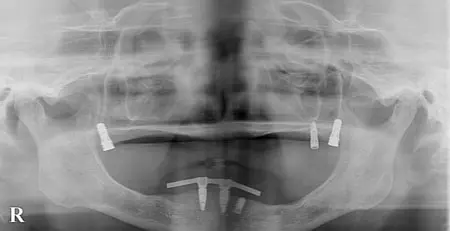

インプラントセラミック

2026.04.0550代男性 欠損していた下左右奥歯にインプラントを埋入してしっかりと噛めるように治療した症例